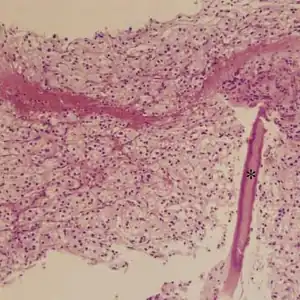

| Micrograph of an alveolar soft part sarcoma, showing the characteristic alveolar-like architecture and cells with eccentric nuclei and abundant eosinophilic cytoplasm. H&E stain. | |

ASPS' histomorphologic features include an alveolar-like pattern at low magnification and the presence of large cells with abundant eosinophilic cytoplasm and eccentric nuclei. Calcifications are commonly present, as may be seen with slow-growing neoplasms.